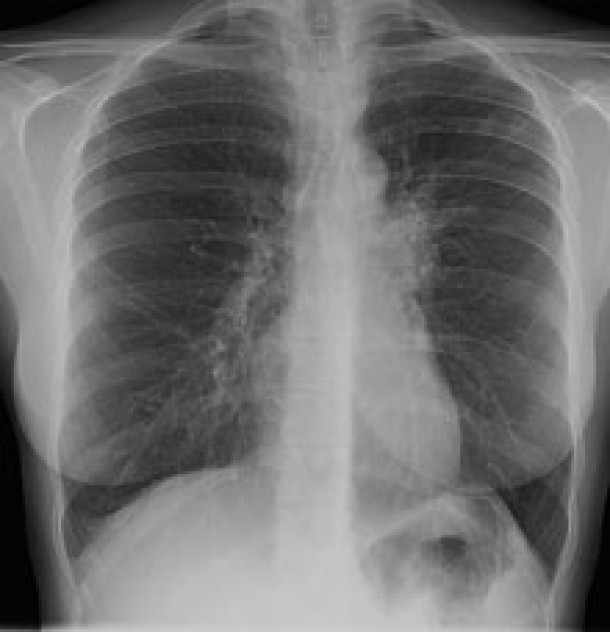

In lume, la fiecare zece secunde, un om moare de tuberculoza. La fiecare patru secunde, un om se imbolnaveste de tuberculoza. Fiecare bolnav de tuberculoza netratata poate molipsi anual de la 10 la 15 persoane - in primul rand pe cei apropiati din familia bolnavului. Aproape 80 la suta dintre bolnavii de tuberculoza au varste de 15 - 45 de ani", a declarat specialistul, miercuri, in cadrul conferintei de presa privind TBC.

In Romania, sunt inregistrate anual 27.500 cazuri noi, iar peste 100.000 sunt rude ale celor bolnavi care fac acesta maladie.